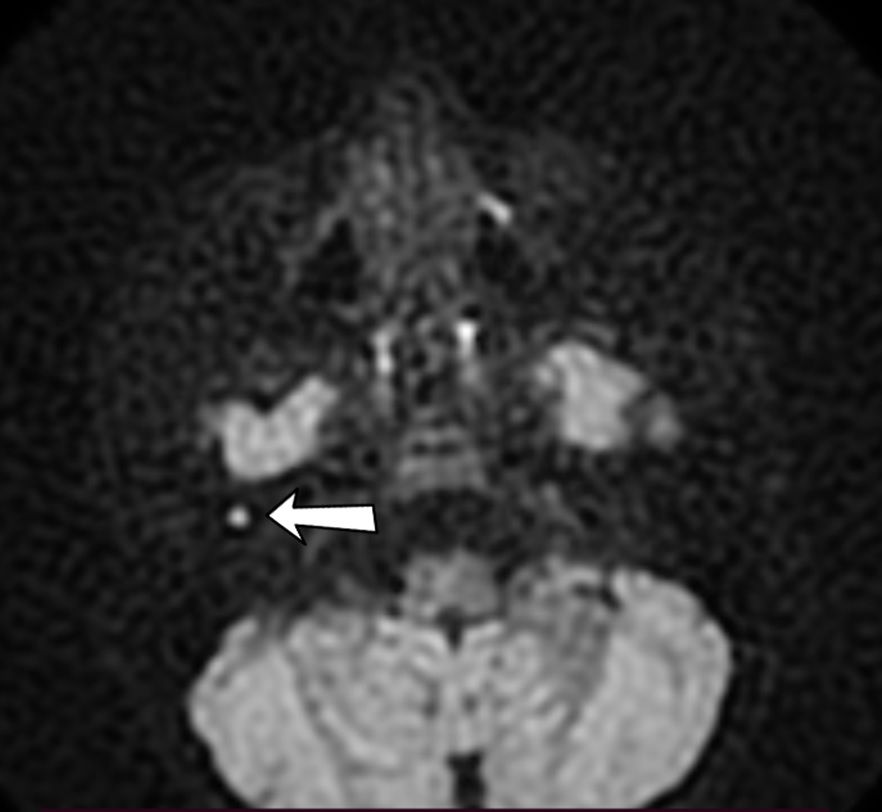

МРТ среднего уха в DWI режиме «протокол холестеамтоа». Холестеатома отмечена стрелкой